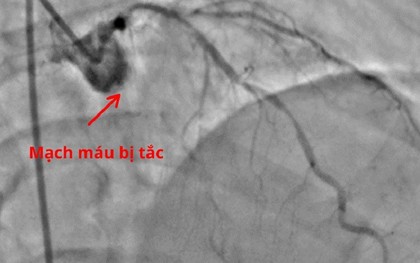

Chỉ vì nhầm lẫn cơn đau âm ỉ vùng thượng vị với rối loạn tiêu hóa thông thường, người đàn ông đã bất ngờ ngừng tim, chết lâm sàng ngay tại nhà. Các bác sĩ khuyến cáo, đau thượng vị, đau ngực mơ hồ, khó chịu vùng bụng trên thường là những dấu hiệu nguy hiểm.